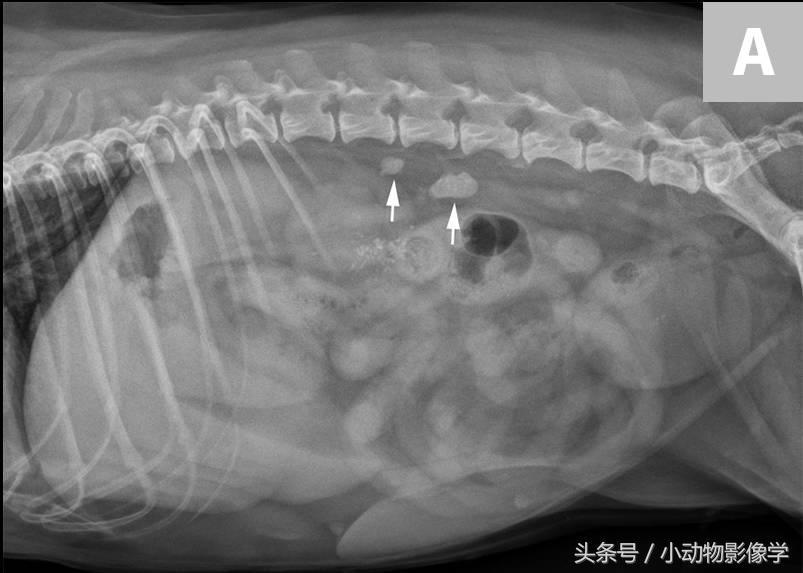

图5A、犬腹部侧位平片,可见腹膜后隙后方和肾脏背侧有两个界限清楚的椭圆形矿物化不透明重叠影像(箭头)。结合腹背位正片(这里没有显示),这些结石可能与右输尿管相关。

图5B、图5A中犬的超声图像,证实了矿物化结构位于右侧输尿管内。可见输尿管显著扩张(三角箭头之间),及输尿管腔内的两个结石引起的远端声影伪像(S)。